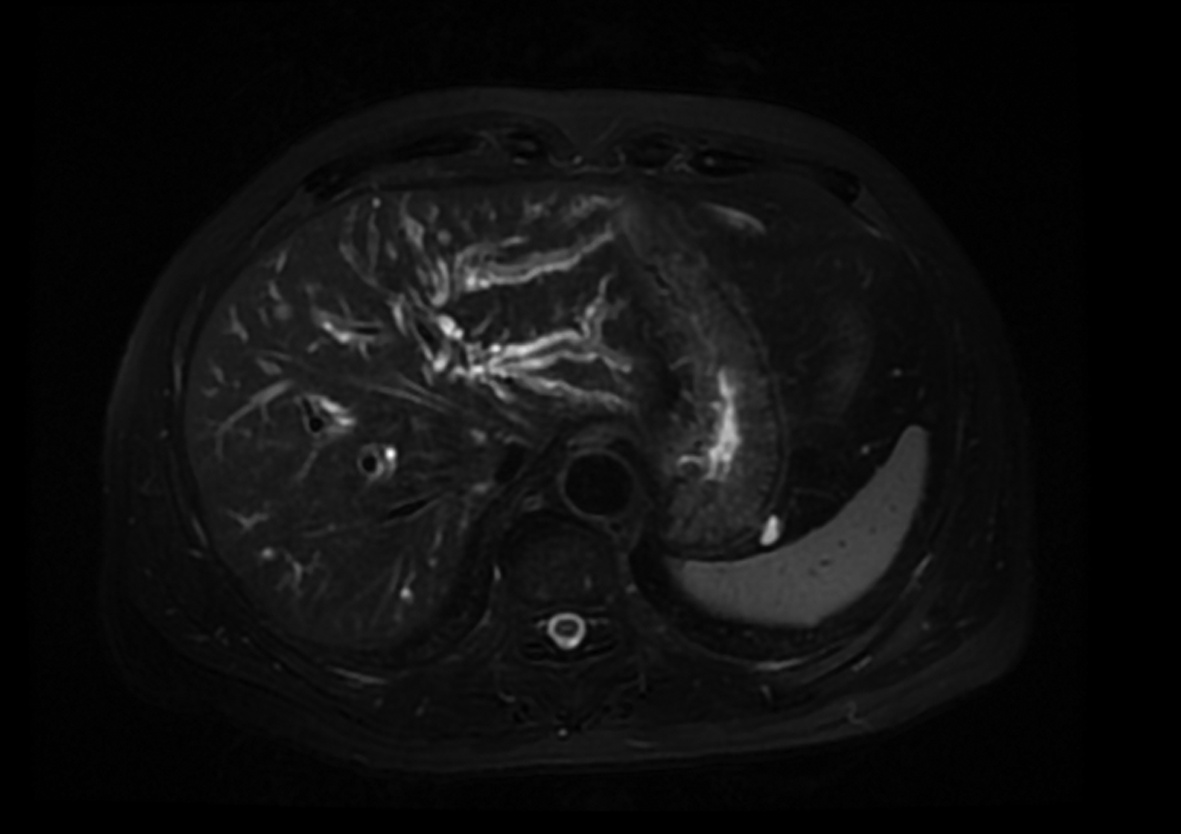

肝移植术后自发性肝破裂出血1例报告

马健, 何力宏, 王凌云, 翟亚楠, 李汛, 张磊

2022, 38(4): 891-893. DOI: 10.3969/j.issn.1001-5256.2022.04.030

摘要(1069) HTML (365) PDF (3041KB)(59)

摘要: